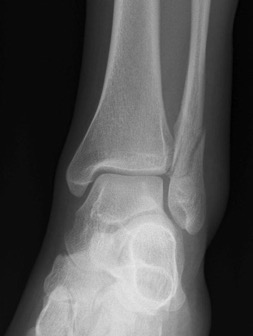

# cheville: score de Weber

Fracture de type Weber A : fracture en-dessous de la syndesmose ; l`articulation est encore mobile.

Fracture de type Weber B : fracture à hauteur de la syndesmose ; souvent le ligament est touché à cause d'un mouvement de rotation mais l`articulation peut encore être mobile.

Fracture de type Weber C : fracture au-dessus de la syndesmose ; le ligament est déchiré à cause d'un mouvement de translation latérale.